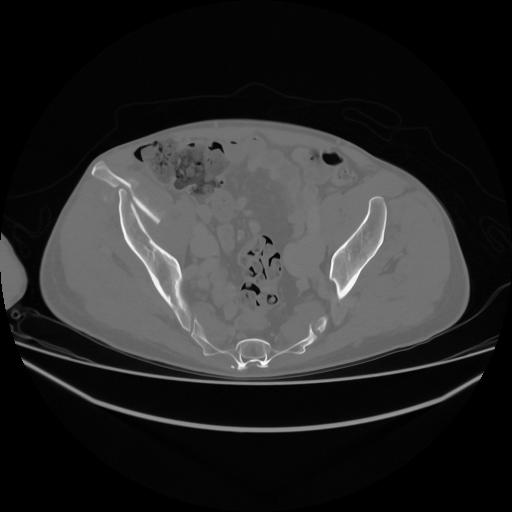

5 CUERPO,CE,Vol,1.0,CUERPO,,